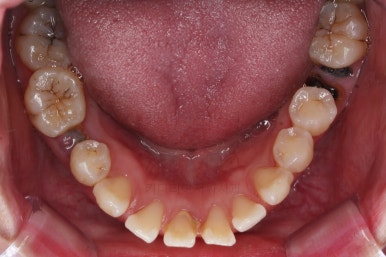

1. 초진

초진 시 입안의 모습입니다.

당장 눈에 띄는 부분은 아래 앞니 사이에 틈새가 있어 치석도 많이 쌓여있는 상황이고요.

윗니-아랫니를 각각 보면 치아가 썩고 부러져 뿌리만 남은 치아가 많이 보입니다.

남은 치아들도 곳곳에 충치가 보이고요.

또 전반적으로 앞니가 앞으로 밀려나와 뻐드러져 있는 모습도 관찰되네요.